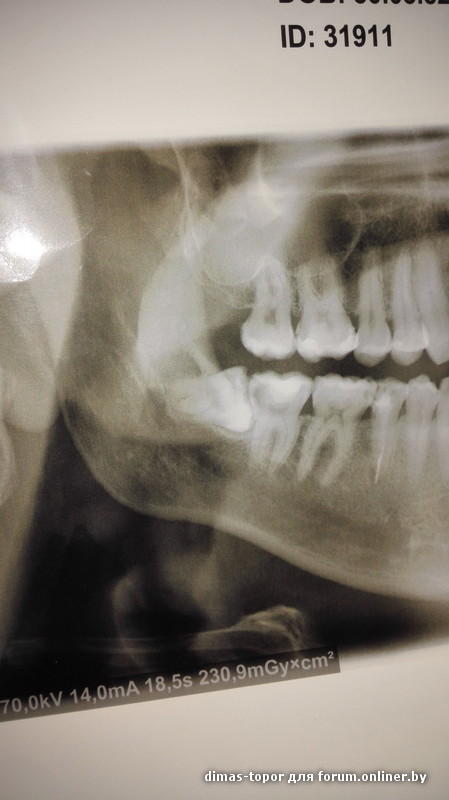

dimas-topor:

Ребята,здравствуйте!посоветуйте хирурга хорошего,надо удалить нижний зуб мудрости,вся проблема в том,что он вырос ,,лёжа,,.кто хорошо удаляет такие проблемные зубы?

aleksall, был у хирурга,сказал,что операция сложная минут на 40.....

Уважаемые форумчане,и в догонку вопрос,действительно ли это ,,сложное,, удаление? Надо ли этот зуб разпиливать/резать десну?или всё не так страшно?

сложности не вижу. Может и за 10 минут выйти.))

удаление не страшное, а страшности в распиливании чего-либо или разрезании нет. не наворачивайте себя не нужной информацией.

ультразвуковой наконечник, который кость режет- используется вместо бора, долота и молотка.

в вашем случае возможно понадобится возможно нет.